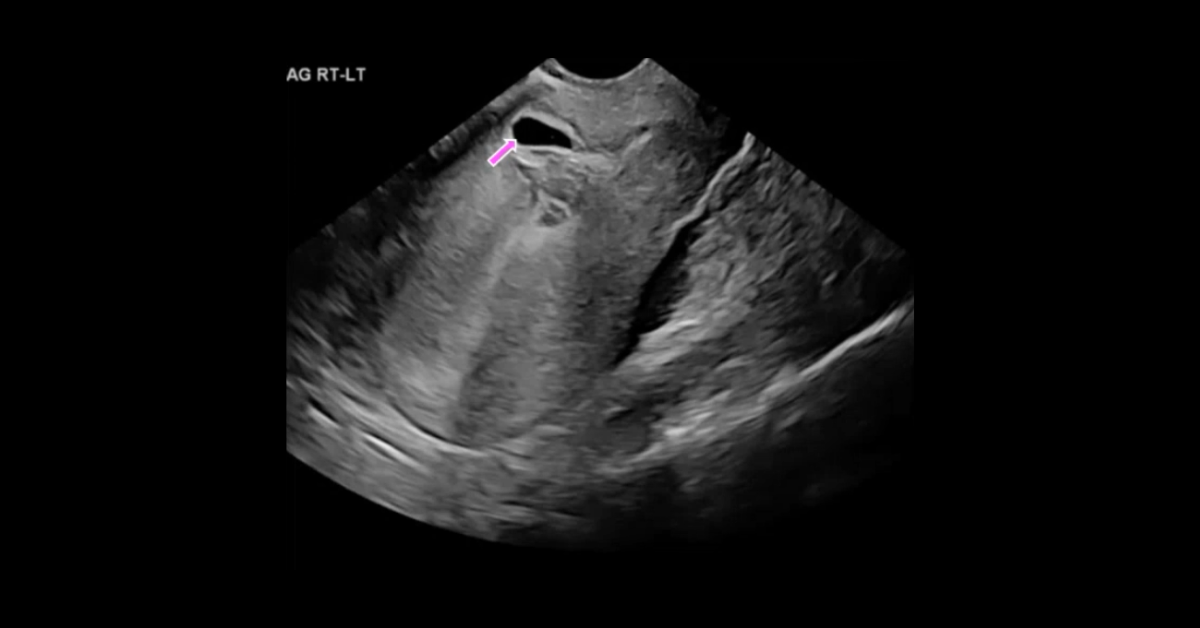

Presented by Ashish Khandelwal, MBBS, MD at Practical Radiology 2025. This talk will allow you to understand appropriate use of multimodal imaging in pregnant patient and know the imaging features of commonly encountered acute abdominopelvic conditions during pregnancy.